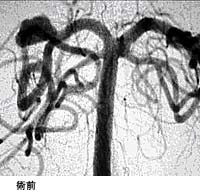

破裂脳動脈瘤に対するGDC(コイル)塞栓術

術後 コイルにより動脈瘤が写らなくなりました。